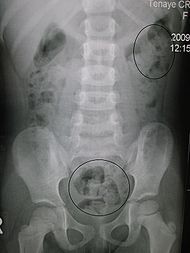

اكثر قریب به اتفاق افرادی كه یبوست دارند، با درمانهای معمولی خوب می‏شوند. وقتی یبوست شدید باشد و بیمار با درمان‏های معمول بهبودی پیدا نكند لازم است بررسی دقیقتری از جمله اندازه‏گیری مدت زمان عبور مواد از روده بزرگ را با

عكسبرداری مخصوص انجام گردد. در این بررسی معمولاً بیمار تعداد 60 عدد از قرصهای كوچكی را می‏خورد و پس از چند روز با عكسبرداری ساده شكم طول مدت عبور مواد از روده بزرگ تعیین می‏گردد. براساس نتیجه این كار در مورد درمان طبی و یا جراحی روده بزرگ تصمیم‏گیری می‏شود.